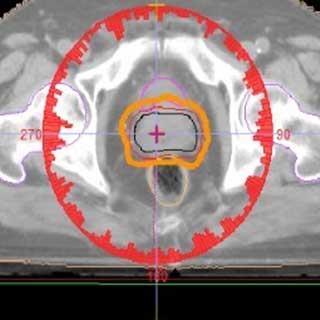

Esto significa que, desde la primera consulta, el Dr. Salinas evalúa a fondo su caso: revisa su diagnóstico, estado de salud general y cualquier otra enfermedad concurrente. Luego, en colaboración con físicos y dosimetristas médicos, crea un plan de tratamiento personalizado que maximice el impacto en el tumor y reduzca el riesgo para el resto del cuerpo